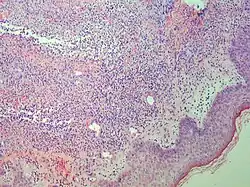

| Prevesicular stage of bullous pemphigoid | Image at right shows influx of inflammatory cells including eosinophils and neutrophils in the dermis (solid arrow) and blister cavity (dashed arrows), and deposition of fibrin (asterisks).[15] However, the diagnosis of bullous pemphigoid consist of at least 2 positive results out of 3 criteria:[19]

|